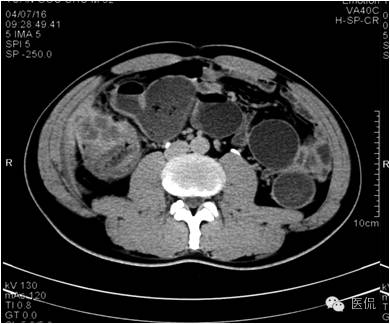

延迟期密度略有降落,但仍有强化,形态不规则。

手术病理诊断:

肝炎性假瘤,侵及周围结肠和腹壁,浸润组织有水肿,粘连。